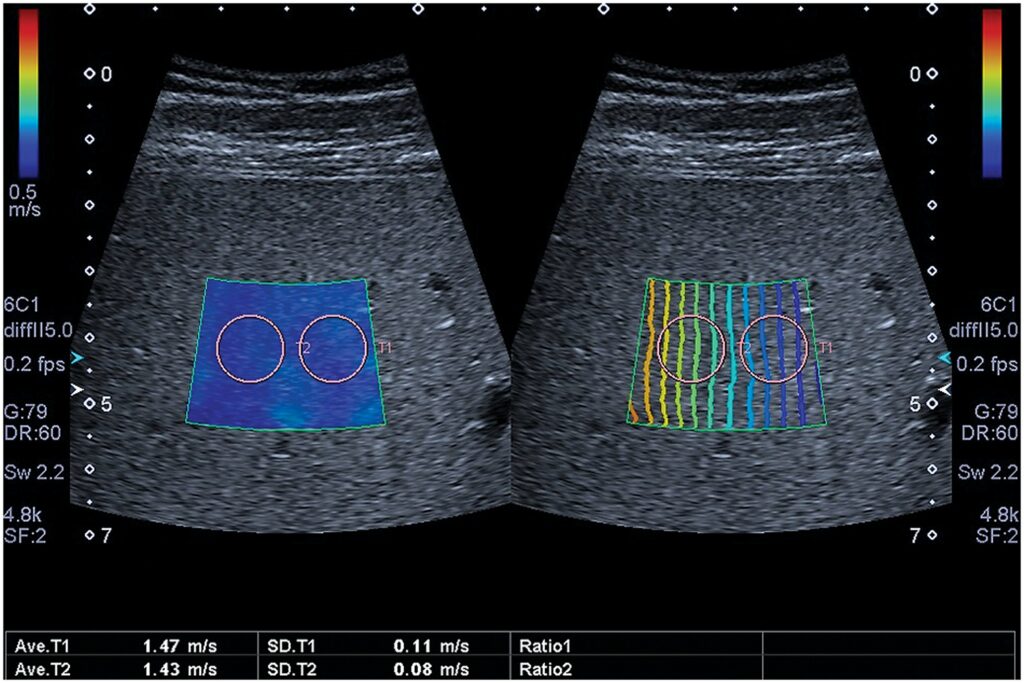

Dažu pēdējo gadu laikā aknu elastogrāfijas pielietojums ir būtiski attīstījies; jaunu elastogrāfijas metožu ieviešana (pārejošā elastogrāfija, punkta bīdes viļņa elastogrāfija,...